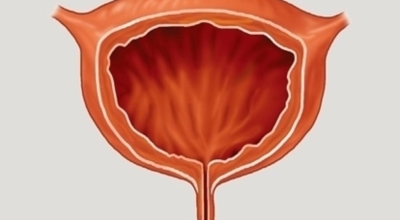

방광

방광은 몸으로 섭취된 물이 신장을 통해 소변으로 배출되기 전에 저장되는 곳을 말합니다. 소변은 온몸을 돌고 온 혈액이 신장에서 걸러져 나온 부산물로서 성인의 1.5~2L가량 만들어진다고 합니다. 이렇게 생성된 소변은 요관을 통해 방광으로 이동하게 되고 소변이 어느 정도 차게 되면 대뇌로부터 배뇨 신호를 받아 방광의 출구가 열리면서 소변으로 배출하는 배뇨 활동을 합니다. 방광에 문제가 생기면 배뇨 활동에 영향을 주어 소변이 새거나 안 나오는 증상부터 혈뇨 등에 문제가 발생합니다.